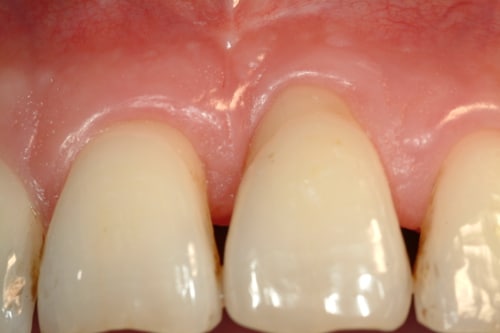

Recessione gengivale in paziente adulto

BlogGengive

Recessione gengivale

Read More